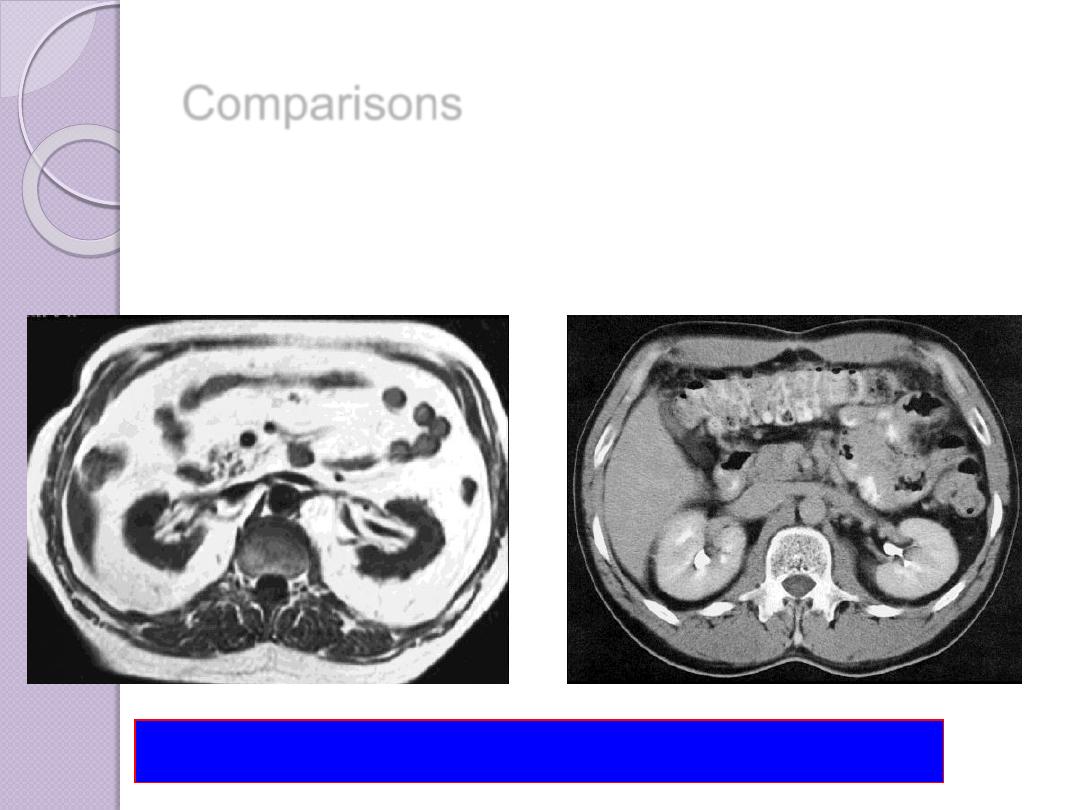

Comparisons

MRI image

CT image

abdomen

Compare bone and soft tissue density